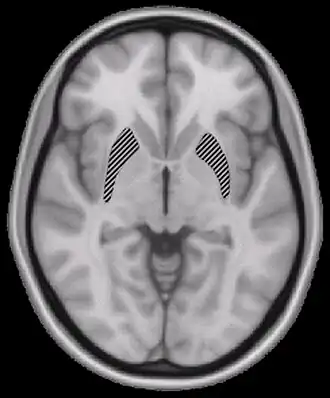

Demência na doença pelo vírus da imunodeficiência humana ou Doença pelo HIV resultando em encefalopatia se refere a uma degeneração cerebral que se desenvolve no curso da doença pelo HIV, mesmo na ausência de qualquer outra doença ou infecção simultânea que possa explicar a presença das características clínicas.[1] Com a invenção da terapia antirretroviral altamente eficaz (TARV) os casos de demência na AIDS diminuíram entre 30-60%.[2]

A degeneração cerebral é causada pelo próprio [HIV] e não por doenças oportunistas. As [vírus|proteínas virais] danificam as células nervosas diretamente ou através da infecção de células inflamatórias no [cérebro] e na [medula espinhal]. O HIV pode, em seguida, induzir essas células a danificar e desativar as células nervosas